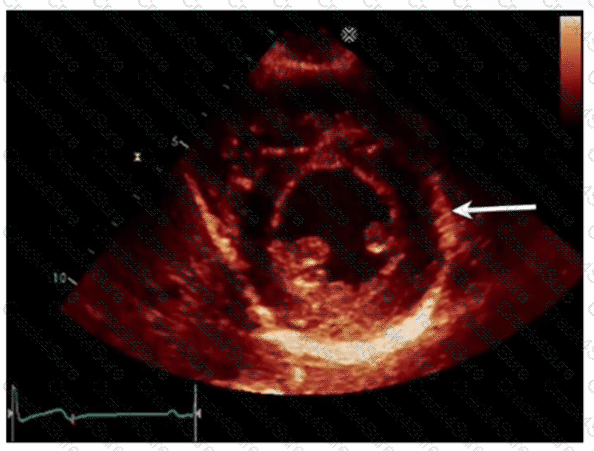

Which left ventricular regional wall segment is indicated by the arrow on this image?

Which phase of the cardiac cycle is indicated by the arrow on this image?